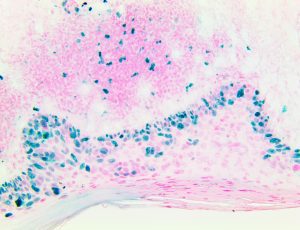

Bio SB has developed high affinity IVD monoclonal antibodies for fast immunohistochemistry (IHC) detection of melanoma, basal cell carcinoma (BCC), squamous cell carcinoma (SCC) and other Mohs surgery related conditions. Combined with our innovative IHC detection systems, we are opening the doors to a faster and more accurate immunohistochemistry applicable to Mohs surgery.

Bio SB has developed a fast, non-biotin monovalent Fab micropolymer IHC detection system for the detection of IVD antibodies for melanoma, BCC, SCC and other Mohs surgery related conditions. Our innovative IHC detection systems have opened the doors for a faster and accurate immunohistochemistry applicable to Mohs surgery.